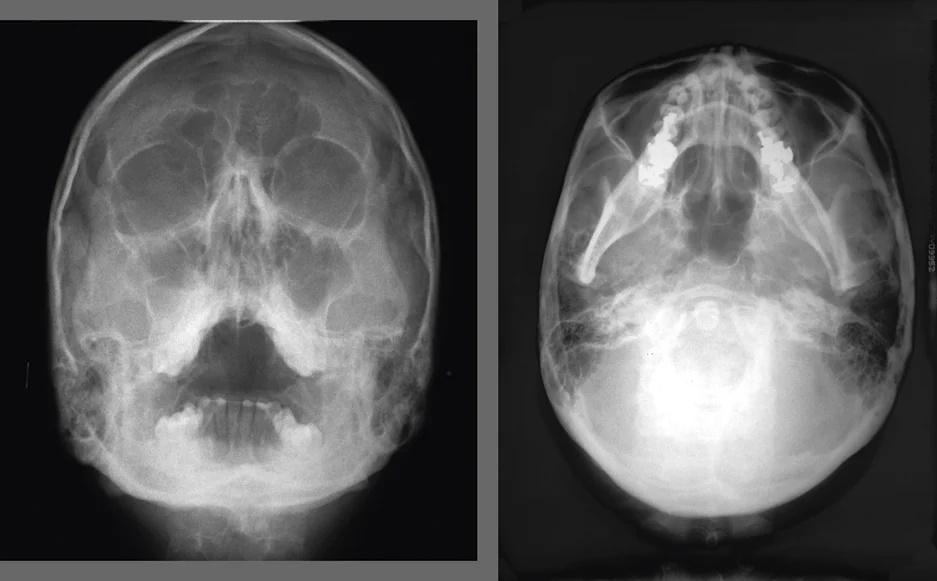

У некоторых цефалостатов, например у комбинированной стоматологической системы GENORAY Papaya 3D Plus предусмотрена съемка в аксиальной проекции. Ее еще называют подбородочной и используют в основном в имплантологии. Она удобна для оценки состояния гайморовых пазух и определения плотности верхнечелюстной костной ткани.

Перед лечением атрофии верхней челюсти, для диагностики опухолевых процессов в верхнечелюстных пазухах, а также в рамках некоторых частных протоколов имплантации рекомендуется съемка в проекции Уотерса. В этом режиме снимок показывает детализированную картину строения и состояния решетчатой и гайморовой пазух. Актуально для хирургов, имплантологов и отоларингологов, работающих в тандеме со стоматологами.